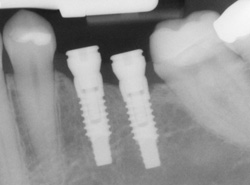

An implant is a synthetic tooth root in the shape of a post that is surgically placed into the jawbone. The “root” is usually made of titanium: the same material used in many replacement hips and knees, and a metal that is well-suited to pairing with human bone. A replacement tooth is then fixed to the post. The tooth can be either permanently attached or removable. Permanent teeth are more stable and feel more like natural teeth.

Implants are versatile. If you are only missing one tooth, one implant plus one replacement tooth will do the trick. If you are missing several teeth in a row, a few strategically placed implants can support a permanent bridge (a set of replacement teeth). Similarly, if you have lost all of your teeth, a full bridge or full denture can be permanently fixed in your mouth with a strategic number of implants.

- Dental implants are surgically placed into the jawbone.